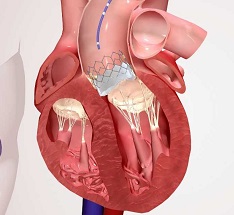

Valve Replacement/Repair

The heart of man contains four valves that direct the blood circulation. Failure of these valves to either open or close correctly results in heart valve disease. It can result in enthusiasm.